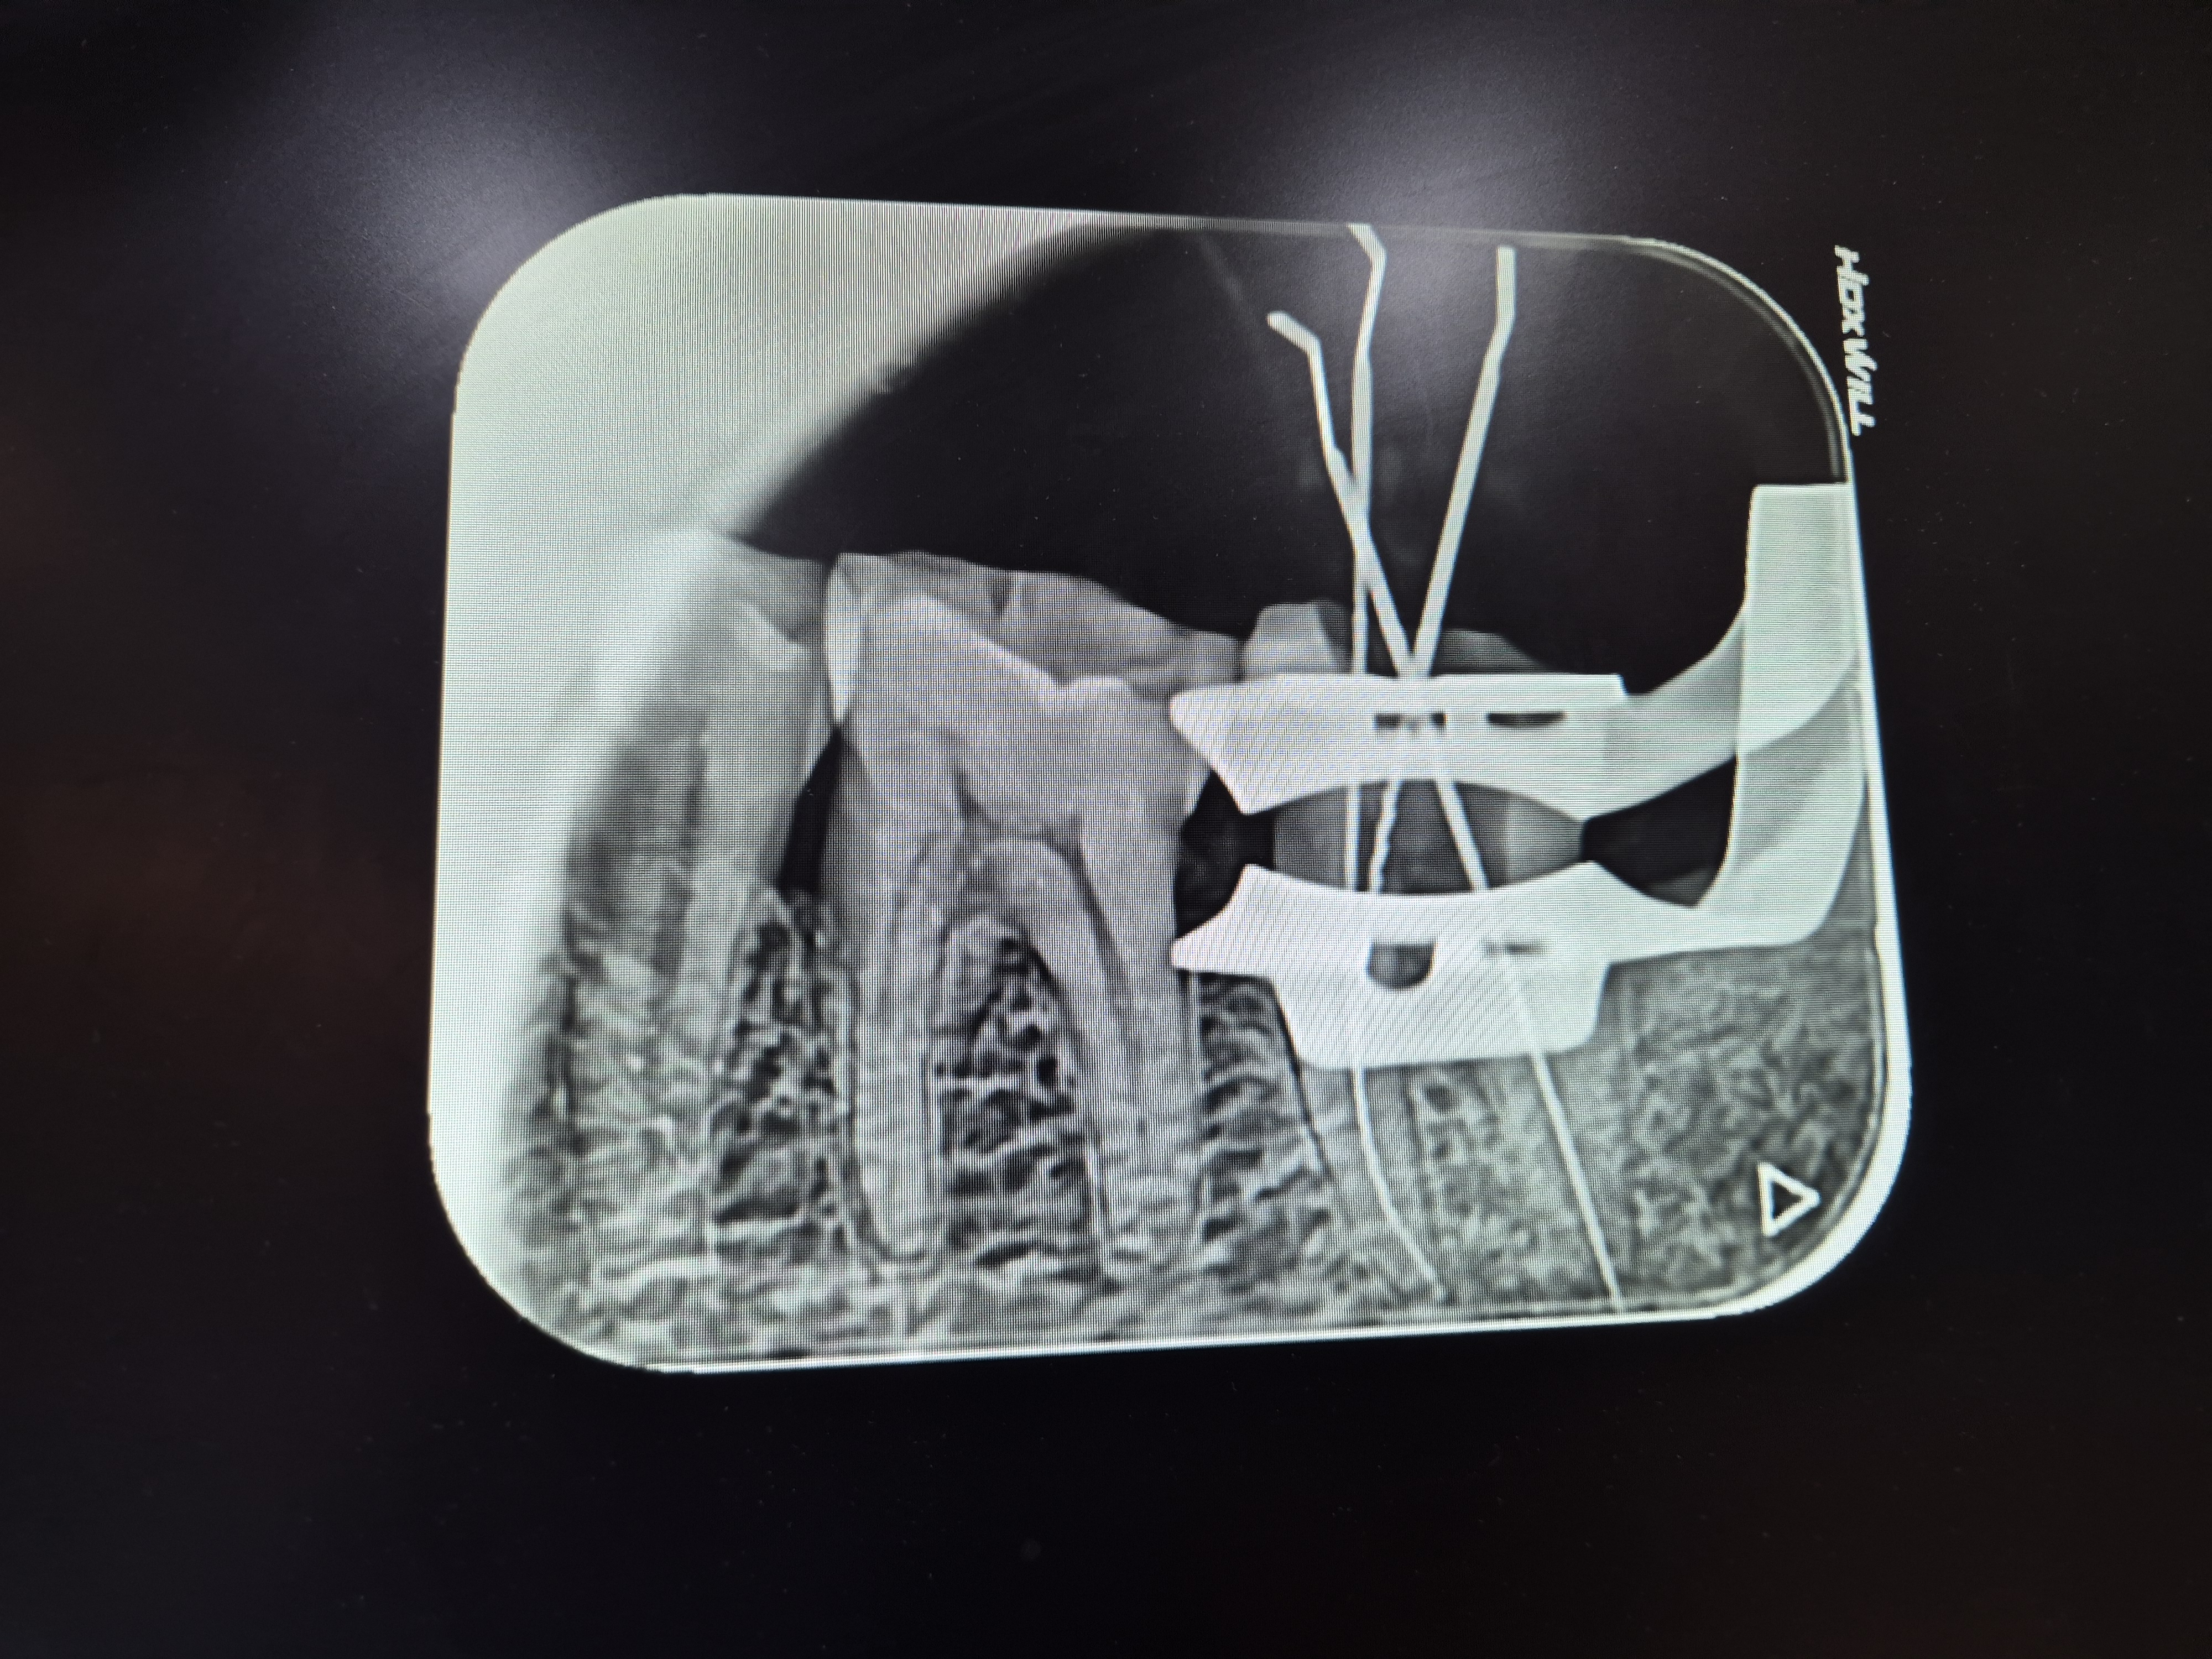

그 후 며칠이 지나도 더욱 아파오니 인근의 병원을 찾아가 사진을 찍고 검진을 받아보니

충치가 생겨 신경치료를 4회정도 받아야한다는 것이다.

치아사진을 보니 5개의 임플란트와 덧씌우거나 치료받은 이빨이 10개정도.

총체적으로 건강하지못한 치아상태이다.